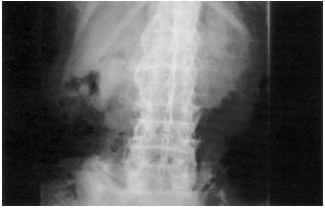

60 47 歲女性患者抱怨腰酸背痛已經十多年,尤其清晨 起床時症狀特別明顯。醫師為其進行 X 光檢查發現 典型之變化如圖,其最可能之診斷為:

(A)退化性關節炎 (B)類風濕性關節炎 (C)僵直性脊椎炎 (D)骨質疏鬆